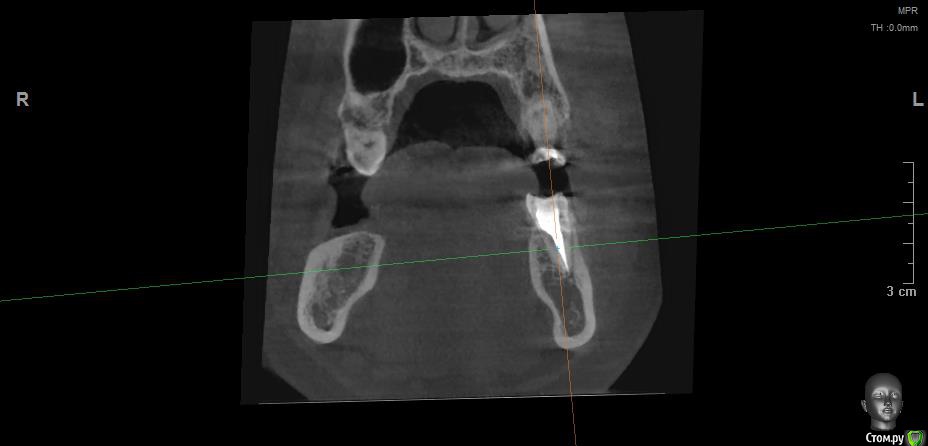

Vords Опубликовано 11 июня, 2020 Поделиться Опубликовано 11 июня, 2020 (изменено) Доброго вечера, профессионалы. Прошу у Вас помощи. Буду очень благодарен за консультацию. 3 недели назад появились боли в в жевательных зубах (около 37 и 36 зубов). В виду того, что боли были достаточно серьезные, а врач, у которого я лечился ранее не мог меня принять из-за пандемии - пришлось идти в городскую поликлинику. По результатам похода был поставлен диагноз пульпит 37 и глубокий кариес 36. На 36 поставили пломбу - 37 успешно депульпировали. На этом история 37 зуба закончена. С 36 после постановки пломбы начались дикие ночные боли и боли при накусывании. На повторном приеме был поставлен диагноз пульпит 36 - поставлено лекарство для умертвления нерва. После этого боль при накусывании прошли. В следующий прием пришел на чистку каналов и пломбировку. Во время этой процедуры я вдруг ощутил совершенно дикую боль (как выяснилось потом - в этот момент и произошла перфорации в области фуркации). Врач ничего не сказал - просто поставил метапекс и запломбировал каналы. В этот момент начались боли при накусывании. а потом постоянная тянущая боль. Продолжалось это около 3 дней - я пошел в другую стоматологию где мне сделали рентген и с подозрение на перфорацию отправили на КТ. По результатам КТ перфорация была подтверждена. С КТ я пришел в городскую стомотологию где мне предложили закрыть перфорацию цементом (pro что-то там - не могу сказать точно). Закрыли ее во вторник на этой неделе. Сегодня восстановили коронку и поставили световую пломбу. Беда в том, что боль при накусывании и "нытье" с этой стороны так и не прошли. По словам стомотолага гос клиники - боль при накусывании из-за метапекса и когда он рассосется - боль пройдет. (до 6 месяцев). Я прилагаю рентген (ужасное качество), фото КТ и ссылку в облако на КТ. Я допускаю, что никто не захочет лезть в облако и тратить свое время на просмотр на КТ (сам не могу разобраться с программой, что бы сделать достойные скрины), но если вдруг у кого-то найдется время - буду очень благодарен. Рентген сделан сразу после пломбировки канала. КТ через 3 дня после этого. В связи с этим вопрос. Возможно ли, что боль при надавливании пройдет если подождать пока рассосется метапекс или это пустая трата времени? Мне стоит ждать какое - то время или в этой ситуации мне поможет только удаление? Благодарю Вас за уделенное время Ссылка на КТ https://cloud.mail.ru/public/44WE/2JeTfXmr2 Изменено 11 июня, 2020 пользователем Vords Ссылка на комментарий

krokomot Опубликовано 11 июня, 2020 Поделиться Опубликовано 11 июня, 2020 Судя по всему у вас в 6м зубе выведен не только метапекс но и гуттаперчевый штифт, скорее всего, если это не исправить боли сохранятся, и что там с коронкой не понятно, на кт сильные тени из-за большого объема рентгеноконтрасного материалла, а прицельный снимок что вы сделали, сделан не поп правилам и на нем сильные искажения, понять трудно что с коронкой. Короче, зуб с перфорацией , выведенным материалом за апексом и гуттаперчей, и при этом еще и беспокоит, прогноз сомнительный. возможно всё можно переделать и всё станет нормально , но это не точно. Вам нужен грамотный доктор эндодонтист. 1 Ссылка на комментарий

wladdX Опубликовано 11 июня, 2020 Поделиться Опубликовано 11 июня, 2020 (изменено) Скриншоты Изменено 11 июня, 2020 пользователем wladdX 1 Ссылка на комментарий

Vords Опубликовано 11 июня, 2020 Автор Поделиться Опубликовано 11 июня, 2020 (изменено) WladdX, огромное спасибо Вам за потраченное на скрины время. А то я так и не смог освоить эту программу (рукалицо). У меня даже есть ощущение, что я вижу теперь штифт, о котором говорил krokomot (хотя и не факт)))) Изменено 11 июня, 2020 пользователем Vords Ссылка на комментарий